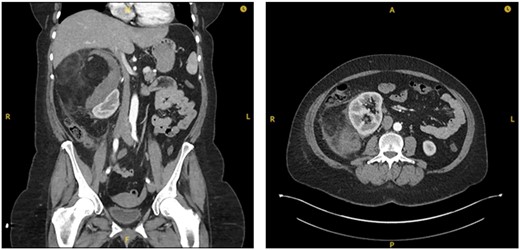

On interval CT scanning, the adrenal lesion was shown to have decreased in size (14.3×13.2 cm), likely due to reduction of intralesional haematoma, and no active haemorrhage identified (Fig. 3). There was an incidental finding of filling defects in the right lower lobe pulmonary artery. The patient was therefore re-admitted to work-up for PE. The patient was asymptomatic of venous thromboembolism. A CTPA identified bilateral segmental and sub-segmental pulmonary vessel filling defects, with no evidence of right heart strain. This therefore warranted commencement of anticoagulation; however, the patient remained at risk of re-haemorrhage of the adrenal lesion. On discussion with different relevant specialties and after counselling the patient on the risks and benefits, it was decided to commence on treatment dose Enoxaparin (low-molecular weight heparin). Due to her higher propensity of haemorrhage, the patient remained as an inpatient for close observation of signs of haemodynamic compromise. The patient remained well on Enoxaparin and was eventually discharged.

Interval CT imaging showing decrease in size of lesion and surrounding haematoma.